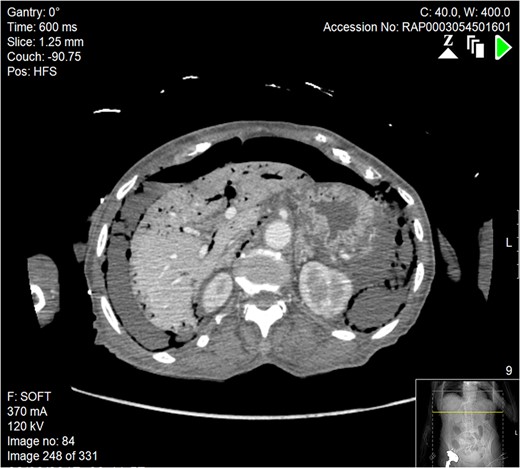

Axial section of abdominal CT scan. There is a significant quantity of free air and fluid within the abdomen, which can be seen adjacent to the liver, indicative of bowel perforation. Free air can also be seen in the portal venous system of the liver.

Subsequently a computerized tomography scan was performed of her chest, abdomen and pelvis (CTCAP), showing hepatic portal venous gas (HPVG), with visible air fluid levels (Fig. 1). There was a large amount of free air and free fluid within the abdomen and pelvis, highly suspicious for perforation (Fig. 2). There was also partial ischaemia of liver segment seven.